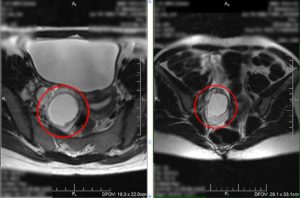

МРТ

Дифференциальная диагностика делает необходимым проведение магнитно-резонансной томографии (МРТ). Данный вид обследования базируется на воздействии магнитного излучения высокой частоты на интересуемую область.

Задача исследования – получение снимков новообразования в разной плоскости. Метод является одним из самых точных и детально визуализирует мягкие ткани и органы. МРТ позволяет определить характер капсульного содержимого, место расположения образования, степень воздействия на соседние органы.

Является важнейшим методом дифференциальной диагностики (дифференцирование дермоидной кисты верхнего века от мозговой грыжи, мукоцелей).

При магнитно-резонансной томографии (в отличие от КТ) не применяются рентгеновские лучи, поэтому данный диагностический метод может быть назначен для исследования тератом у детей, выявления дермоидной кисты при беременности.

- Дермоидная киста яичника мрт — данная процедура позволяет в случае сомнений подтвердить диагноз: во время МРТ жировая ткань зрелой тератомы становится различимой.

Магнитно-резонансная томография

В отличии от интракраниальных липом, которые соответствуют жиру на всех последовательностях, интракраниальные дермоидные кисты имеют более разнообразные сигнальные характеристики [4]:

- T1

- обычно гиперинтенсивные (за счет холестерола)

- капельные включения в субарахноидальных пространствах при разрыве

- T1 с контрастным усилением

- обычно не имеет усиления

- выраженное усиление оболочек при химическом менингите, после разрыва кисты

- T2: варьирует от гипо- до гиперинтенсивного